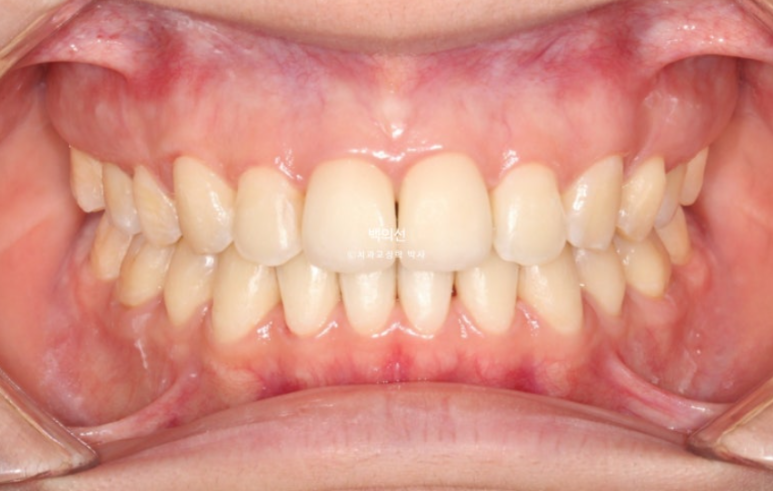

인비절라인 장치제작을 위해 클리피씨 장치를 제거한 직후입니다.

25.02

아직 맞지 않는 중심선은 남은 공간이 닫히면 자연스레 맞아질 것 입니다.

아까 엑스레이에서 치축이 기울어져 있던 파란화살표 측절치는 튀어나와 보이고 기울어져 보입니다.